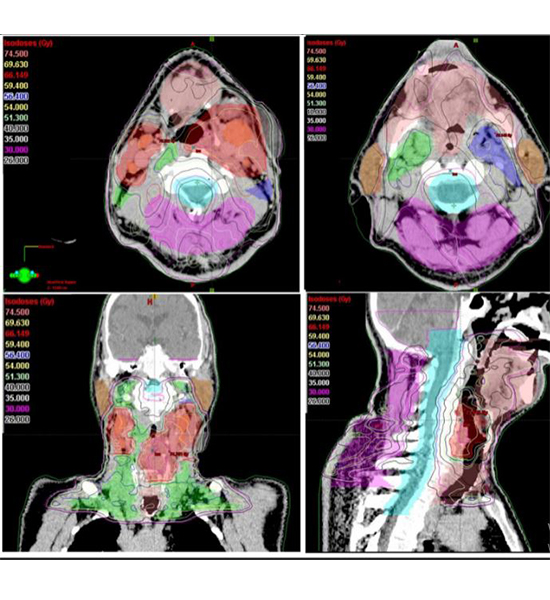

Radyoterapiye başlanmadan önce, radyasyon onkoloğu doktorlar tarafından bir hastanın bilgisayarlı tomografi (BT) veya manyetik rezonans (MR) görüntülerinin incelendiğini ve hastalığın net bir şekilde gözlenebilir kısmı olan ana tümörün ve civardaki sağlıklı normal dokuların hacimlerinin çok dikkatlice belirlendiğini anlatan Dr. Yavuz: “Tümör ve çevredeki normal dokuların üç boyutlu olarak sınırlarının çizildiği (konturlama) bu süreç, bir hastanın tümör bölgesine ne kadar radyasyon alacağını ve ışının en uygun nasıl odaklanacağını belirler. Örneğin: Hastada bir baş ve boyun kanseri varsa, bu, çevredeki hassas dokuların varlığı nedeniyle özellikle çok hassas bir çalışmayı gerektirir. Görüntüleme yöntemlerinden yararlanarak ışınlanması ve ışınlanmaması hedeflenen hacimlerin sınırlarını üç boyutlu belirlemek, konturlama yapmak kişiden kişiye, doktordan doktora oldukça farklı gerçekleştirilmekte. 2017 yılında, Utrecht Üniversitesi'nden yapılan büyük bir çalışmada, kendi alanında çok deneyimli radyasyon onkolojisi uzmanı doktorların aynı hastanın bilgisayarlı tomografi (BT) filmlerine göre hedeflenen tümörleri ve normal dokuları oldukça değişken bir şekilde çizerek belirledikleri, hatta bazı doktorların meslektaşlarından sekiz kat daha fazla oranda yüksek riskli klinik hedef hacimlere karar verdikleri gösterilmiş. Bu durum, hastalar için en iyi tedavi kararının verilmesinin garanti edilememesini, hastalar için ideal bir radyoterapi standardı oluşturmada ortada bir sorun olduğunu göstermektedir” dedi.

Bu sorun’un aşılmasına yönelik olarak Dr. Yavuz şunları söyledi: “Son aylarada, özellikle A.B.D.nin Ulusal Sağlık Enstitü’sünce desteklenen önemli bir araştırma projesinde Yapay zeka (AI) kullanarak yüksek riskli tümör hedef hacimlerinin sınırlarının 3 boyutlu olarak belirlenmesi için her bir görüntüleme film kesitinde tümör ve normal doku sınırlarının tek tek çizilmesi (konturlama) işlemlerini otomatikleştirmek için yeni bir yöntem geliştirildi. Dünyanın en önemli Kanser Merkezlerinin başında gelen A.B.D.nin Texas eyaleti, Houston şehrindeki M.D. Anderson Kanser Merkezi önderliğinde yapılan bu çalışmada, bu merkezdeki onbinlerce kanser hastasının radyoterapi planlaması kayıtlarından yararlanarak, bu merkezde çalışmış ve çalışmakta olan yüzlerce doktorun hedeflenen tümör hacimlerinin ve normal dokuların sınırlarını çizerken (konturlarken) ne şekilde davrandıkları, karar verirken hangi tercihlerde bulundukları üzerinde durulmuş. Örneğin, MD Anderson'da tedavi edilen 52 ağız-boğaz kanser hastasından elde edilen veriler incelenip dünyadaki birkaç baş ve boyun alt-uzmanlık branşlaşmasını sağlayabilmiş, yani sadece baş-boyun kanserleri radyoterapisi ile uğraşan çok tecrübeli ve özel bir ekibe sahip olan MD Anderson'daki radyasyon onkolojisi doktorlarının hedef hacimleri nasıl belirlediklerine odaklanılmış. Yüksek riskli hedef hacimler için çoğu zaman doktorların sadece ana tümörün sınırlarını çizdiklerini ve komşu normal dokuların şekline göre farklı farklı bir emniyet mesafesi belirledikleri görülmüş. İlk önce basit uzaklık vektörlerini kullanarak bunu araştırmaya başlamışlar. Çevredeki normal anatomik yapılardan ana tümör hacminin uzaklıkları ve mesafe haritası bilgilerini kullanarak yüksek riskli tümör hacimlerin bir parçası olan vokselleri, üç boyutlu pikselleri tanımlar şekilde verileri toparlamışlar. Sonuçta, eldeki verileri idealize ederek yüksek riskli tümör bölgelerini en doğru ve otomatik bir şekilde belirleyen gelişmiş bir yazılım üretmişler. Yapay Zeka uygulaması şeklinde belirlenen bu hacimler ile alanındaki en tecrübeli doktorların belirlediği hacimler arasında çok büyük bir uyum saptandığı gibi, hekimden hekime ve hastadan hastaya değişebilen hacim belirleme farklılıkları da ortadan kalkmış ”.